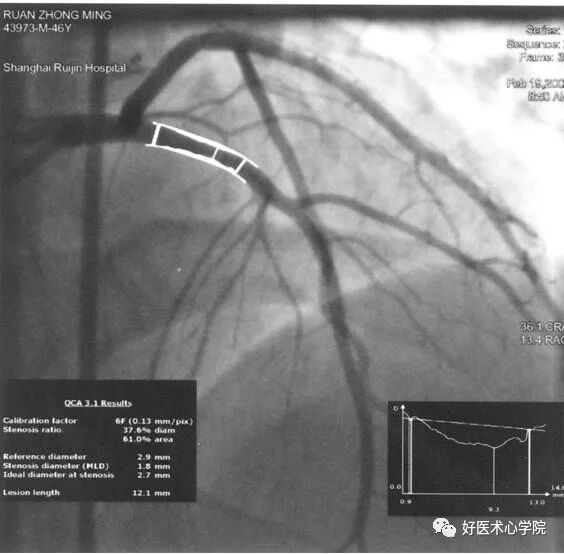

9. 侧支循环(Collateral Circulation)

当冠状动脉严重狭窄或阻塞时,近端灌注压明显下降,刺激侧支循环形成,血管远端被侧支循环逆向供血而显影。

造影导丝是什么珍藏 冠脉造影从流程到诊断,基础必备!_https://www.jmylbn.com_新闻资讯_第96张

侧枝:右冠脉→左前降支